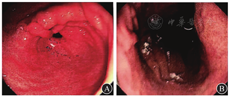

患者女,52岁,因"腹胀、嗳气等上腹部不适,加重1个月"于2018年3月13日就诊于空军军医大学西京医院消化内科门诊。查13C-尿素呼气试验(13C-urea breath test,13C-UBT)阳性,予以阿莫西林联合克拉霉素的铋剂四联疗法进行根除治疗。2018年4月27日复查13C-UBT仍为阳性,提示幽门螺杆菌根除治疗失败;于2018年5月27日行包含呋喃唑酮联合四环素在内的铋剂四联方案进行补救治疗。2018年7月3日,复查13C-UBT阴性,提示幽门螺杆菌根除成功;行胃肠镜检查提示慢性萎缩性胃炎,以胃体为著;肠镜检查未见异常。患者排便量少,上腹部不适稍有缓解,无腹胀,继续给予雷贝拉唑、马来酸曲美布汀胶囊、复方消化酶等对症治疗后好转。患者平素体健,无高血压、糖尿病等慢性病史,无吸烟、饮酒史,其父既往诊断为胃癌。鉴于患者为胃癌患者的一级亲属,嘱其1年后复查胃镜和病理活体组织检查(以下简称活检),重点关注胃体变化。2019年5月13日,患者在空军军医大学西京医院复查13C-UBT提示阴性,胃镜检查结果(图1)提示胃黏膜欠光滑,以胃体部明显,色泽相间明显,黏膜下血管纹透见,散在点片状糜烂和陈旧性出血斑;胃体、胃角和胃窦部多发灰白色微隆起,部分表面略凹陷、发红,窄带内镜观察见亮蓝嵴样改变,多系肠化生。分别在胃体上段大小弯侧、胃角和胃窦大小弯侧取材,组织质软、蠕动正常,黏液湖微浊。病理检查结果(图2)提示胃体上部大小弯侧出现黏膜中度慢性炎,重度萎缩,重度肠化生;胃角和胃窦部大小弯侧黏膜出现中度慢性炎,中度萎缩,轻度肠化生。胃炎评价系统(operative link on gastritis assessment, OLGA)/基于肠化生的胃炎评价系统(operative link on gastritis assessment based on intestinal metaplasia, OLGIM)分期为Ⅳ期/Ⅲ期。诊断:慢性萎缩性胃炎伴重度肠化生。患者伴有腹胀、嗳气等上腹部不适,予以口服羔羊胃提取物维B12胶囊(新疆生化药业有限公司,55 U/粒,2粒/次,3次/d)治疗。治疗1个月后,于2019年6月18日复诊,患者腹胀、嗳气等上腹部不适症状较前明显改善,嘱其坚持羔羊胃提取物维B12胶囊治疗。治疗半年后,于2019年12月11日复查13C-UBT呈阴性。胃镜检查结果(图3)提示贲门下大弯侧可见片状黏膜浅凹陷,底无苔,边缘黏膜尚光滑,略充血,取材处组织质软;胃体下段小弯侧可见片状黏膜微隆起,顶端糜烂,取材处组织质软;余胃黏膜尚光滑,柔软,色泽红白相间,窦部散在点片状黏膜红斑,蠕动可,黏液湖微浊。2019年12月11日病理活检结果(图4)提示胃体下段黏膜中度慢性炎,轻度急性活动,中度萎缩,中度肠化生,小凹上皮增生;贲门黏膜慢性炎急性活动,小凹上皮增生伴中度肠化生;胃窦、胃角黏膜轻度慢性炎,轻度急性活动,轻-中度萎缩;胃体上段黏膜轻度慢性炎。OLGA/OLGIM分期为Ⅲ期/Ⅱ期。诊断:慢性萎缩性胃炎伴肠化生。患者胃黏膜萎缩和肠化生程度较前减轻,嘱其继续口服羔羊胃提取物维B12胶囊治疗,半年后复查。因疫情影响,患者2020年6月未按时复诊,坚持羔羊胃提取物维B12胶囊治疗至2021年3月。2021年3月30日复查13C-UBT阴性。胃镜结果(图5)提示贲门局部黏膜充血;余胃黏膜柔软欠光滑,以胃体小弯侧明显,色泽红白相间明显,黏膜下血管纹透见,蠕动正常,黏液湖微浊。分别于胃体上段大小弯侧、胃角和胃窦部大小弯侧取材,组织质软。病理活检结果(图6)提示胃窦、胃角黏膜中度慢性炎,轻度急性活动,轻度萎缩,小凹上皮增生;胃体黏膜轻度慢性炎。OLGA/OLGIM分期为Ⅰ期/0期。诊断:慢性萎缩性胃炎,贲门炎。经羔羊胃提取物维B12胶囊治疗1年半,患者胃黏膜OLGA分期从Ⅳ期降至Ⅰ期,OLGIM分期从Ⅲ期降至0期,提示羔羊胃提取物维B12胶囊能有效降低CAG伴肠化生患者的OLGA和OLGIM分期,并有可能降低患者的胃癌发病风险。